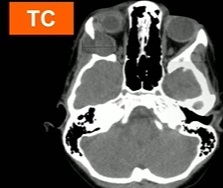

trauma a 3 meses

hemangioma capilar